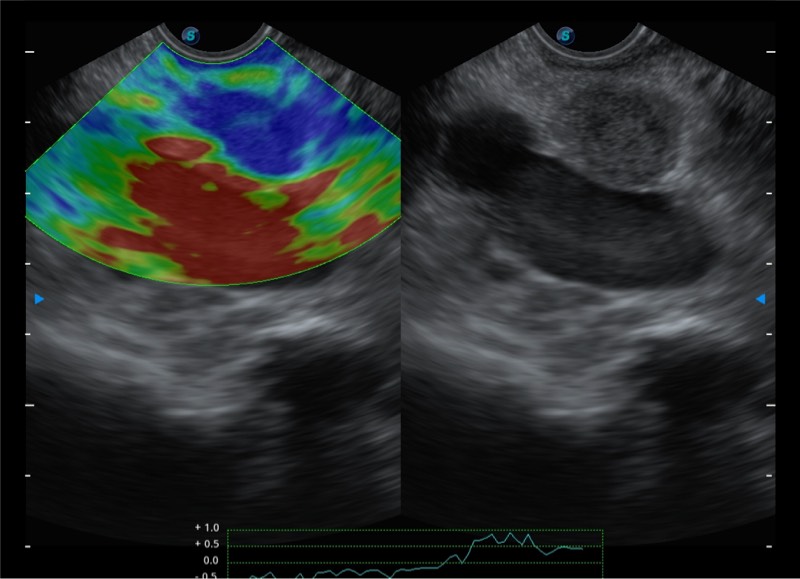

基于二十年的超声技术积累,MILE米乐集团官网提供了最新一代的独立超声主机,在提供高质量图像的同时满足多学科使用。具备常见多普勒技术并提供弹性成像、声学造影等高端影像技术。新一代传感器具有更强的抗干扰能力并减少图像伪影。